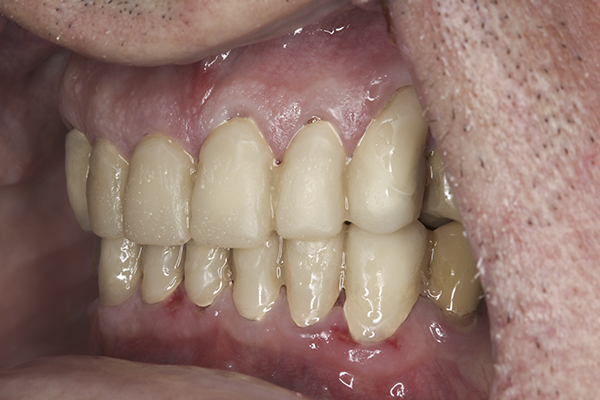

(35.) Postoperative right lateral, closed view.

Figure 35

(36.) Postoperative anterior, closed view. Note the position of the upper and lower canines to provide canine guidance.

Figure 36